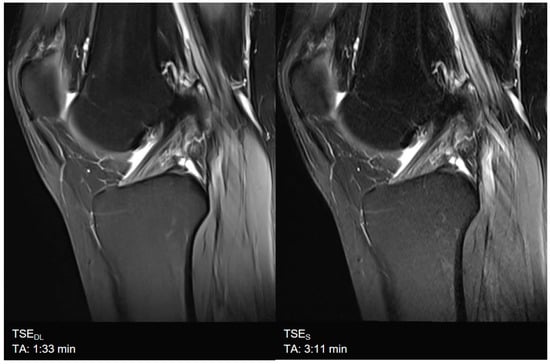

| Knee | TSES | TSE PD FS | coronal | 3:11 | 150 | 0.2 × 0.2 × 3.0 | 2 | 1 | 3 | 3790 | 44 | 150 | 100 | 14.6 |

| sagittal | 3:11 | 150 | 0.2 × 0.2 × 3.0 | 2 | 1 | 3 | 3790 | 44 | 150 | 100 | 14.6 | |||

| TSEDL | TSE PD FS | coronal | 1:33 | 150 | 0.5 × 0.5 × 3.0 | 1 | 1 | 3 | 3580 | 41 | 150 | 120 | 13.7 | |

| sagittal | 1:33 | 150 | 0.5 × 0.5 × 3.0 | 1 | 1 | 3 | 3580 | 41 | 150 | 120 | 13.7 | |||